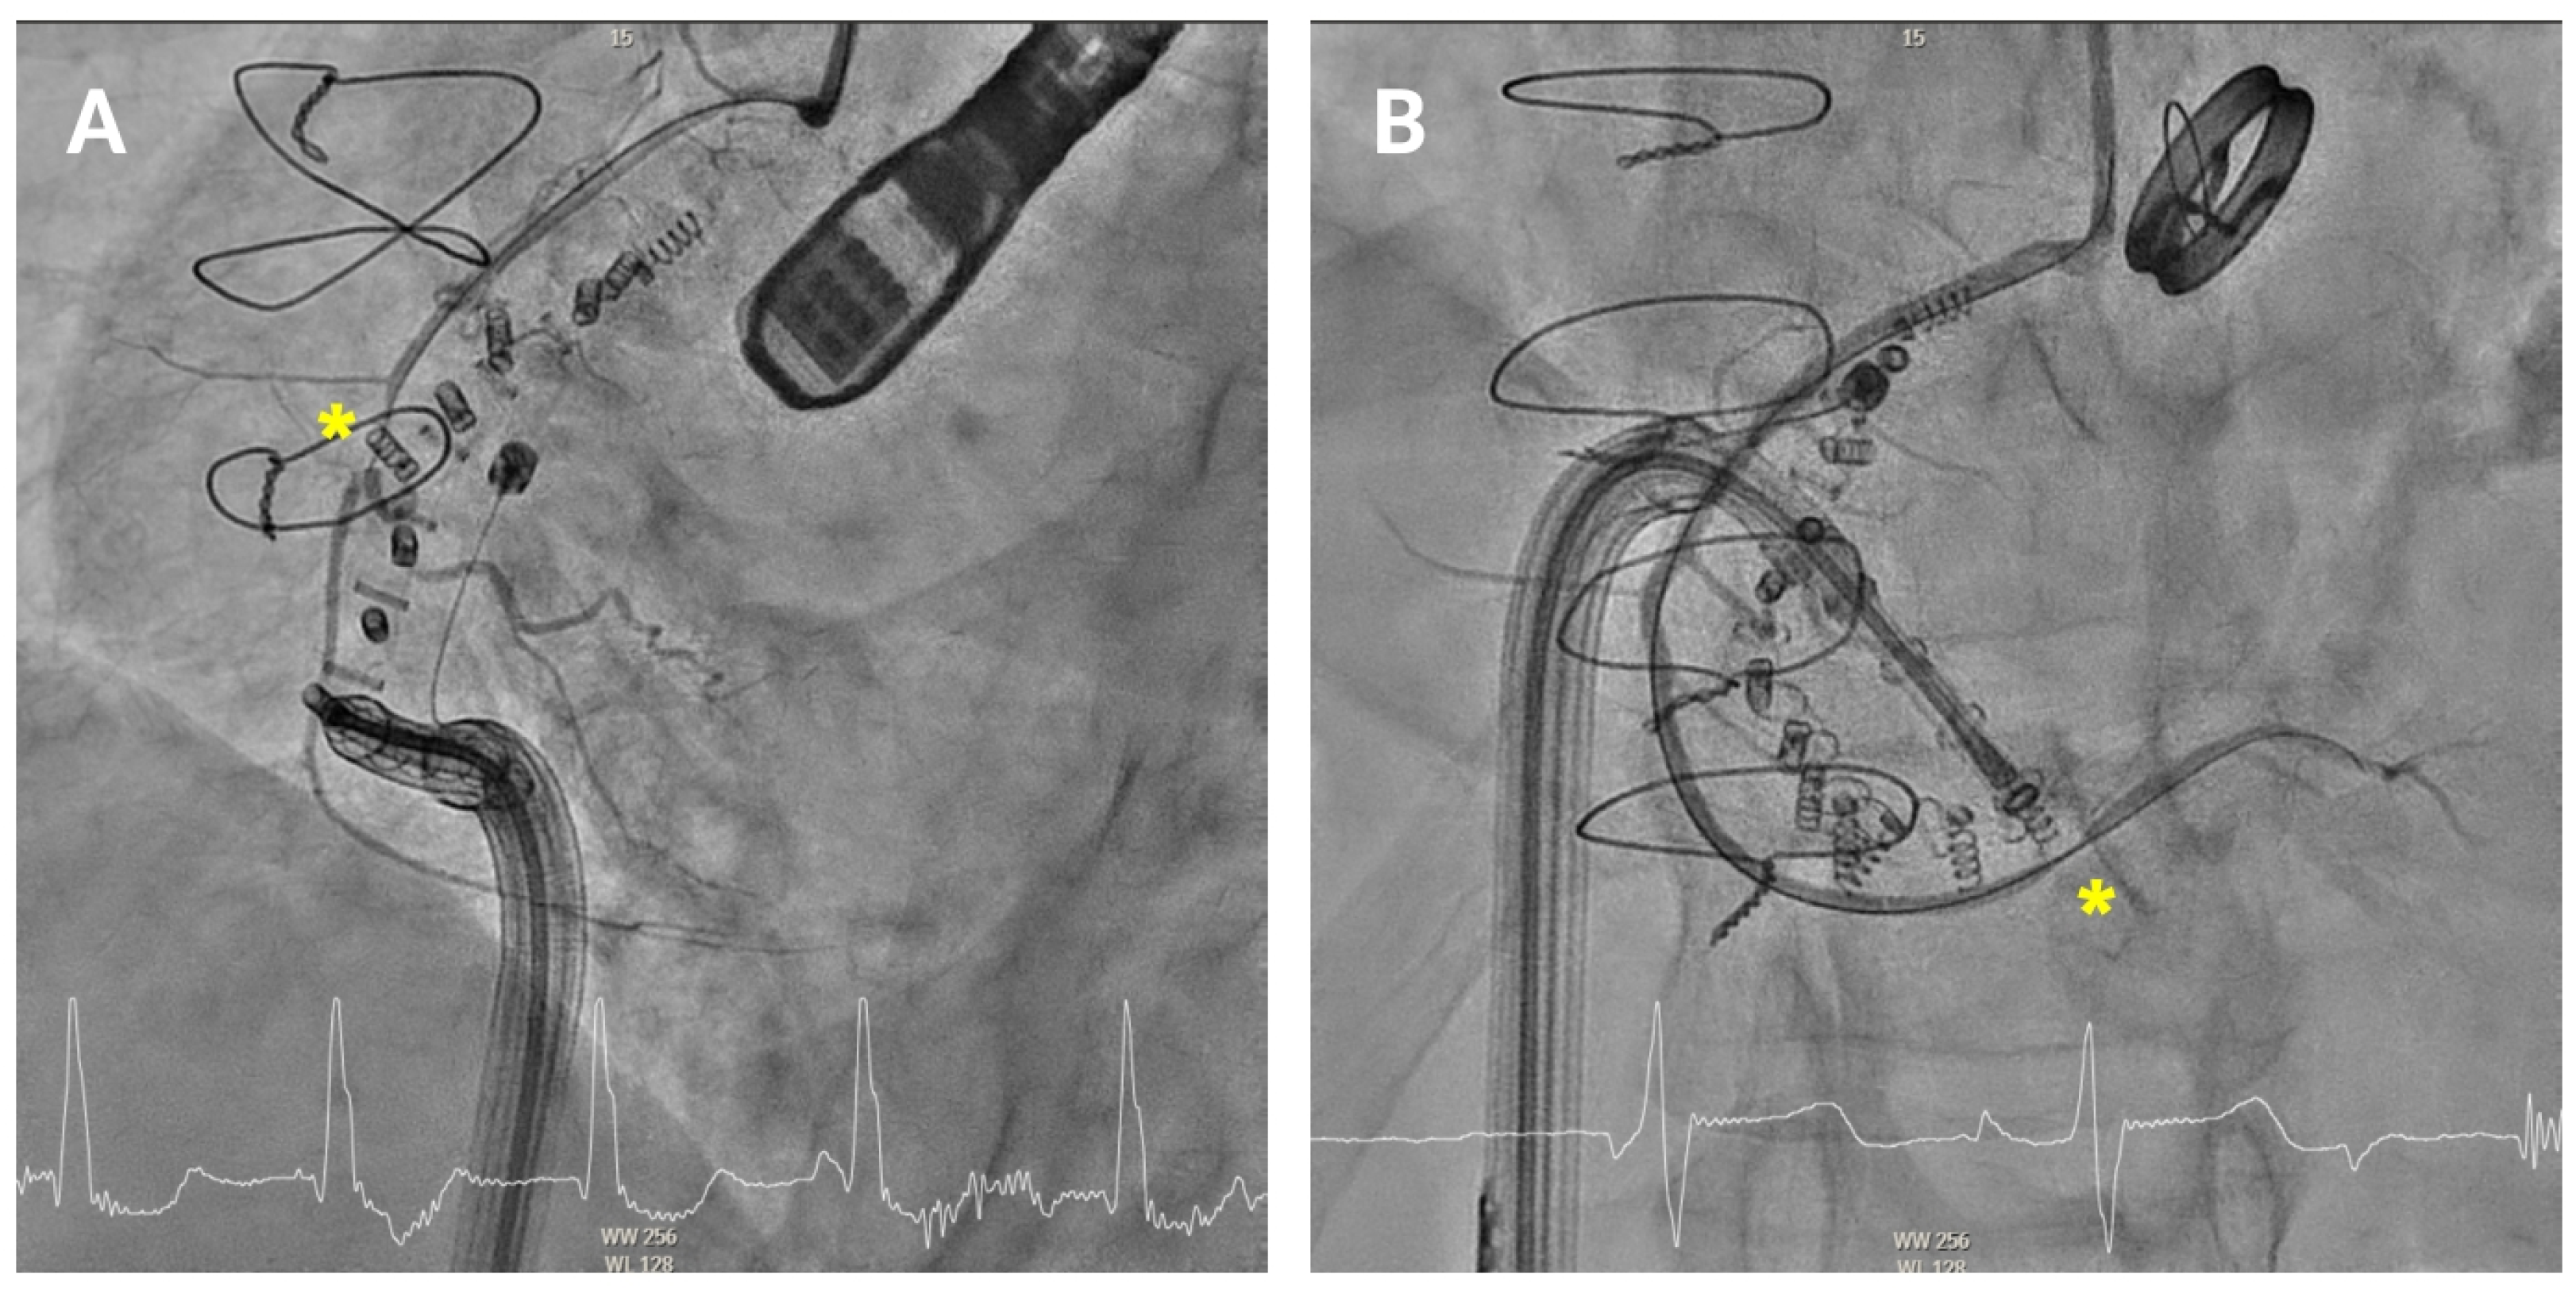

4.3.1. First Anchor Positioning (Anteroseptal Commissure)

The first anchor is positioned in the fibrous tissue anterior to the tricuspid annulus, close to the aorta, at least 25 mm from the center of aortic valve (

Figure 5A). The mid-esophageal right ventricular inflow-outflow view and transgastric right ventricular basal views are used to confirm the orientation of the IC [

10,

11]. It is essential that the IC tip is directed away from the aortic root to avoid complications. Fluoroscopy is performed using the LAO and RAO projections to verify directional accuracy, ensuring that the catheter does not misalign toward the aortic root or the RCA.

4.3.2. Anterior Annulus Anchoring

Once the first anchor is released, the procedure progresses toward the anterior annulus (

Figure 5B). TEE views, such as the transgastric views at 40–60° and mid-esophageal views at 50–70°, provide crucial information for visualizing the IC’s position along the anterior segment of the annulus [

11]. Biplane and multiplanar reconstruction techniques enhance visualization, allowing for more accurate device placement. Fluoroscopically, the RAO projection guides the implant catheter (IC) along the annulus and ensures correct anchor positioning relative to the valvular structures. Before release, a “push–pull” test is performed under combined echocardiographic and fluoroscopic (RAO) guidance. On echocardiography, pulling allows observation of the annulus being drawn toward the IC (

Supplemental Video S1). On fluoroscopy, pulling causes the anchor to move slightly from its original position, resulting in traction of the previously deployed band, anchors, and the RCA wire.

4.3.4. Posterior Annulus (Hooking)

Anchoring along the posterior annulus (

Figure 6A) poses unique challenges due to its parallel alignment with the echo beam and distance from the probe. At this point, the device often needs to be curved in an angle of 90° between the IC and the TSS (“hooking”) to cross the RCA and properly reach the anchor points (

Supplemental Video S2). A mid-esophageal MPR view and a transgastric view at 150° provide a better view of this segment. RAO and LAO projections are employed to verify the alignment of the IC with the annulus and ensure there is no contact with unintended structures [

11]. If loss of coaxiality or echo shadowing occurs, corrective actions include sheath repositioning, modification of LAO/RAO angles, or pre-shaping of the catheter curve.

4.3.5. Posteroseptal Commissure

Finally, as the band approaches the posteroseptal commissure (

Figure 6B), deep esophageal and mid-esophageal bicaval views ranging from 0° to 135° may facilitate visualization of the coronary sinus and the septum, which are critical during this phase [

11]. For final anchors placement, the RAO view helps confirming anchor security and alignment with the valve annulus, while avoiding any potential misalignment or overlap with other structures. Biplane imaging enhances alignment checks and reduces shadowing artifacts.

Figure 5.

Anterior tricuspid annulus anchoring. (A) First anchor placement in the fibrous tissue anterior to the tricuspid annulus, near the aorta. Orientation is confirmed using mid-esophageal right ventricular inflow-outflow and transgastric right ventricular basal views, along with fluoroscopy in an RAO projection. (B) Subsequent advancement of the implant catheter along the anterior annulus through transgastric and mid-esophageal views (40–70°) and multiplanar reconstruction.

Figure 6.

Posterior tricuspid annulus anchoring. (A) Posterior annulus anchoring requires navigating anatomical complexity due to echo beam alignment and distance from the probe. A 90° “hooking” angle between the implant catheter and the transvenous steerable sheath is often necessary to overcome the right coronary artery and access the posterior annular region. Transgastric transesophageal view (150°) and upper esophageal retroflexed views aid visualization, while RAO and LAO fluoroscopic projections confirm alignment and proper catheter trajectory. (B) Final anchoring at the posteroseptal commissure using deep and mid-esophageal bicaval views (0–135°) for visualization of the coronary sinus and septum. RAO projection and biplane imaging help verifying proper anchor placement and avoiding overlap or misalignment with nearby structures.